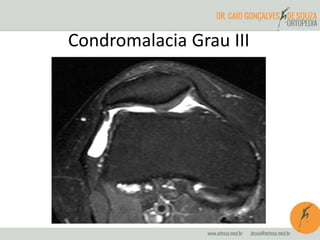

Diagnóstico por imagem

• RM

– Padrão ouro

– Classificação:

• Grau 0: cartilagem normal

• Grau I: área de baixo sinal intracartilaginosa

• Grau II: grau I + alteração de contorno

• Grau III: aspecto serrilhado

• Grau IV: úlceras cartilaginosas e alterações do osso

subcondral

Condromalacia Grau III